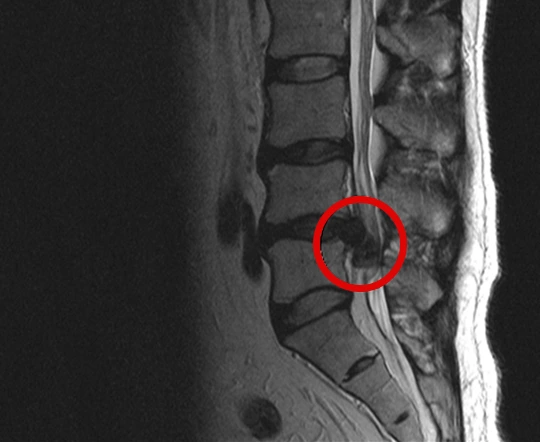

사진출처: 안양 국제 나은 병원 척추센터 자료

허리 디스크는 위 사진처럼 섬유륜이 찢어져 수핵이 탈출되어 신경과 척수를 압박하는 것이다.

촬영 결과 그나마 다행인 것은 아직 내 허리 디스크는 수술을 요하는 정도는 아니라는 것.

5년 전쯤 5번 척추 디스크 확진을 받았다.

이젠 3, 4, 5번에서 퇴행성 척추증이 선명하게 나타난다.

1, 2번 척추는 정상이지만, 이어져 있는 척추다 보니 퇴행성 척추증이 더 심해질 일만 남았다.